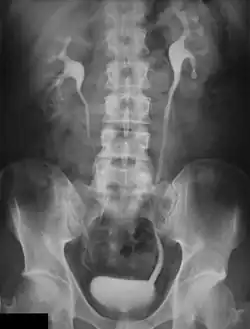

General Radiography

Digital image receptors have been increasingly applied in general radiography since the turn of the century. Early studies indicated its superior image quality relative to film/screen technology in skeletal radiography[1][2]. On this basis, refinements of exposure technique have also occurred[3][4][5][6]. Furthermore, dose comparisons with traditional radiography and various forms of Computed Radiography (CR) with direct and indirect Digital Radiography (DR) have been made[7][8][9]. In addition, the performance of digital image receptors for fluoroscopic applications has also been investigated[10].

Results of these investigations have indicated significant advantages in favour of the digital technology. In general, the change in image receptors has been technically similar to the transition from film-based to digital cameras in photography. However, work practice changes and capital cost are major considerations with the implementation of digital radiography[11].